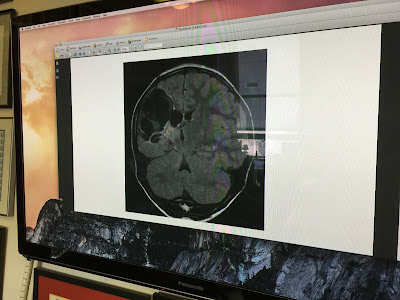

Below are some pictures he showed us of Byron's MRI. The white space that can be seen in the right hemisphere is fluid. According to the MRI , the left hemisphere is completely normal and seems to be doing all the good work.